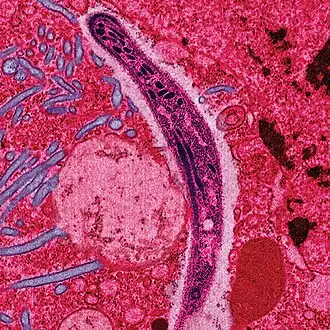

Une maladie infectieuse est une maladie provoquée par l'invasion d'un ou plusieurs micro-organismes ou agent infectieux (bactéries, champignons, parasites, protozoaires, virus) dans un tissu où ils se multiplient, et par une réaction générale des cellules et des tissus infectés pour éliminer ces agents pathogènes ou leurs toxines (processus impliquant notamment le système immunitaire des plantes et des animaux).

L'étude des agents infectieux relève de la biologie, de la microbiologie médicale, de l'épidémiologie et de l'écoépidémiologie. Dans la nature, des maladies infectieuses se développent chez tous les organismes vivants (animaux, végétaux, fongiques, micro-organismes… il existe également des virus de virus[1]). En tant qu'interactions durables, les maladies infectieuses font partie des boucles de rétroaction qui entretiennent la stabilité relative (équilibre dynamique) des écosystèmes, la plupart des pathogènes coévoluant avec leur hôte depuis des millions d'années. Leur mode de transmission est variable et dépend de leur réservoir (humain, animal, environnemental) et parfois de vecteurs (maladies vectorielles).